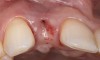

The crown and screw-retained custom abutment were removed, and a surgical cover screw was placed into the implant, thereby allowing spontaneous gingival augmentation in situ (Figure 33 and Figure 34). Note that the lingual aspect of the implant site was significantly more coronal than the labial aspect, which was positive because the defect would be limited to a facial–lingual defect. A fixed RBR bridge was cemented on the adjacent teeth and used as a tooth-supported transitional provisional restoration (Figure 35). A few weeks were allotted to let the soft tissue heal and migrate around the cover screw (Figure 36) to see if there would be complete coverage, thereby allowing a soft-tissue augmentation procedure to be performed with primary flap closure as in clinical scenario No. 2. The major obstacle in achieving a positive tissue response was that the implant depth was also deficient because the implant–abutment connection was at the level of the free gingival margin. It was decided that the best treatment option would be to remove the implant. A high-powered reverse-torque device (Fixture Remover Kit, NeoBiotech, www.neobiotechus.com) was used to remove the implant atraumatically (Figure 38 through Figure 41). The implant socket was allowed to heal for several months not unlike an extracted tooth (Figure 42). A new implant was placed in a better position from both a restorative and esthetic perspective (Figure 43), and after a few months of healing, a new crown was made (Figure 44). A satisfactory functional and esthetic result was achieved (Figure 45 and Figure 46) without employing pink porcelain.

Fig 36. Two weeks after RBR placement, the soft tissue did not adequately cover the implant. The problem was in poor implant angulation and proper depth to allow the soft tissues to cover over.